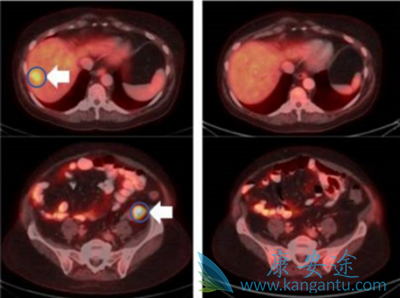

咋看LOXO-101治疗效果显著

此次大会期间,关于该药的最新治疗信息和临床进展着实让人振奋!